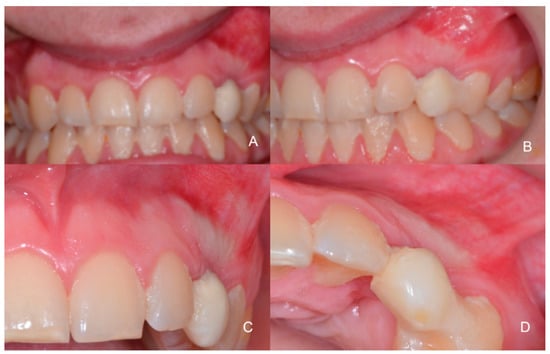

1.1. Case Number 1

1.2. Case Number 2

1.3. Case Number 3